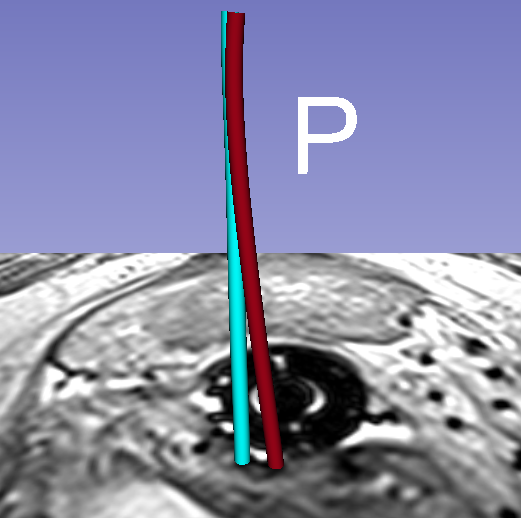

Qualitative results for two different examples can be seen in Fig. 3 and demo movies444https://goo.gl/fLsa2R. The top rows illustrates cross-sectional and 3D rendered views of automated segmentations of a catheter array. The overlap of the colored catheters shows how well they agree. The bottom row of this figure illustrates the case of one particular catheter from the experiments, and specifically how both the model and image guidance are necessary to achieve correct segmentation.